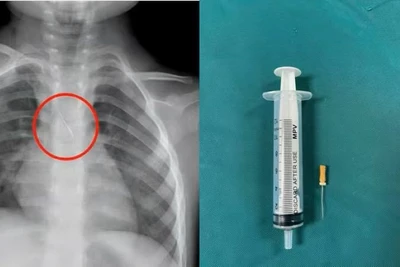

Cái đinh được bác sĩ phẫu thuật lấy ra từ ruột non của bệnh nhân.

Kết quả cho thấy dị vật là một chiếc đinh đã xuyên qua thành bụng trái và găm trực tiếp vào ruột non, tiềm ẩn nguy cơ nhiễm trùng ổ bụng và biến chứng nặng nếu không xử trí kịp thời.

Trước tình trạng nguy cấp, các bác sĩ Khoa Ngoại Tổng hợp đã nhanh chóng chỉ định phẫu thuật nội soi cấp cứu. Ê-kíp tiến hành lấy dị vật, khâu lỗ thủng ruột non, đồng thời khâu phục hồi thành bụng. Sau mổ, bệnh nhân tỉnh táo, các chỉ số sinh tồn ổn định và đang được theo dõi hậu phẫu.